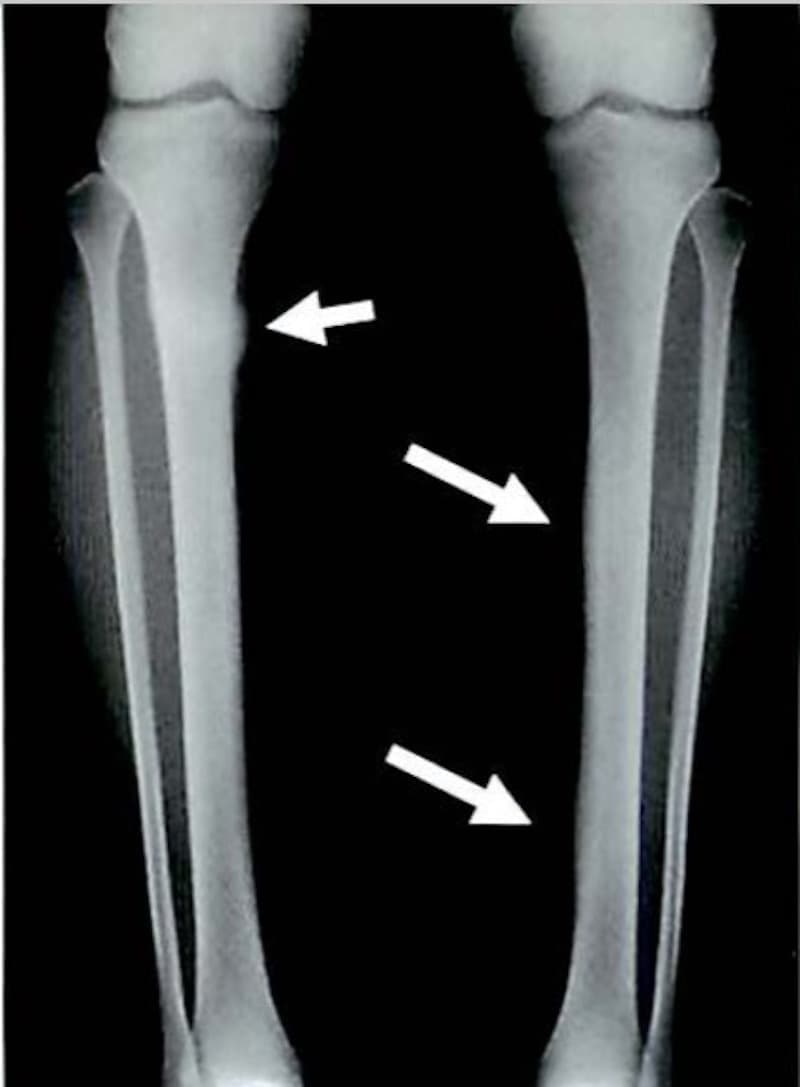

疲労骨折

疲労骨折は健常な骨において同一部位に外力が繰り返されることによって

骨が疲弊し起こる骨折です。

突然起きる骨折とは異なり、ジャンプやダッシュなどの通常のスポーツにより

繰り返される外力が骨に微細な骨折(顕微鏡レベルで確認できる)を引き起こします。

初期は骨がストレスに反応して骨吸収像を呈し、経過するに従い骨吸収と骨新生が

複雑に並存した状態に進んでいきます。

つまり繰り返す弱い力により骨に小さな骨折が引き起こされ、

その状態が慢性的に続くことで大きな骨折に発展するということです。

スポーツの種類により

肋骨(剣道)、頚椎(ゴルフ)、尺骨(バレー、ソフトボール)恥骨(卓球)

脛骨(長距離走、走高跳など)、腓骨(長距離走)、中足骨(短距離走)

などが疲労骨折の好発部位となります。

※ Monthly orthopaedicsから画像抜粋